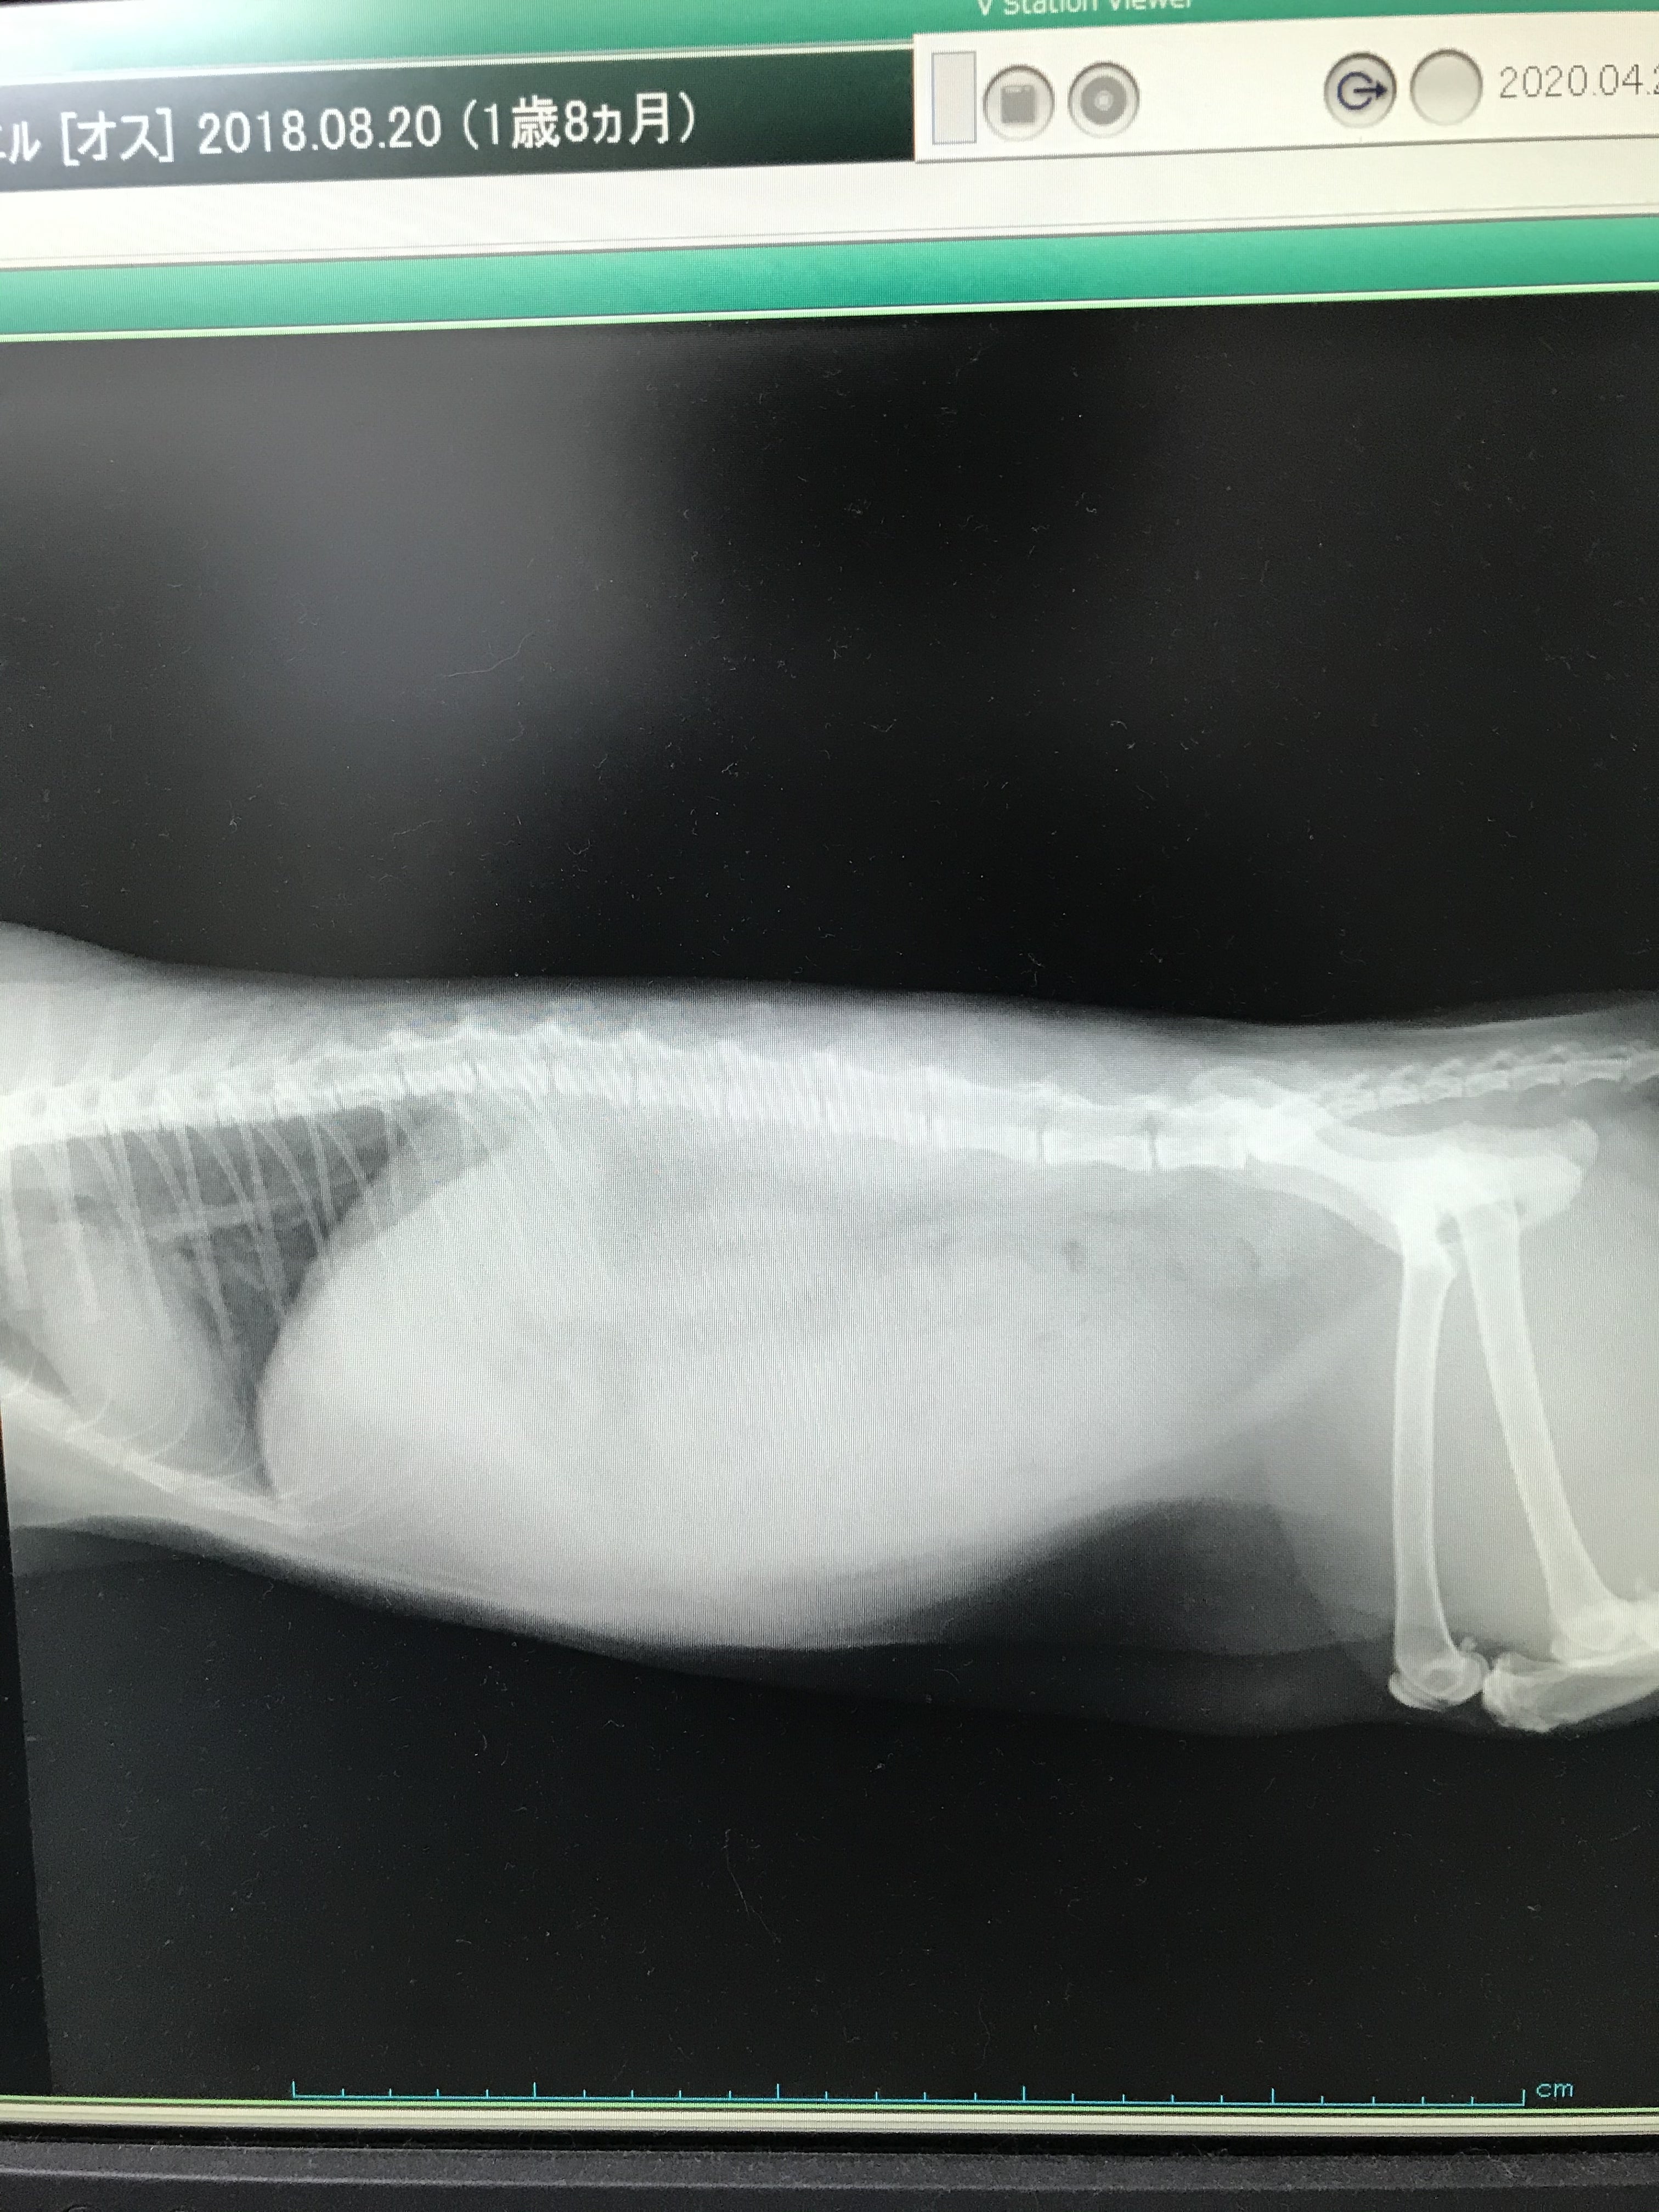

ミエルの場合一番初めに気づいた異変はお腹の張りと食欲不振でした。

腹水がたまり食欲もなくなり水を飲むことも減っていき一日寝たままで過ごし徐々に軽くなりあんなに重たくなったね、大きくなったね、と言っていた体も一回り小さくなり、日に日に背骨は浮き出て不安な毎日でした。

FIPの診断はとても難しくウェットタイプとドライタイプの現時点ではウェットタイプでした。